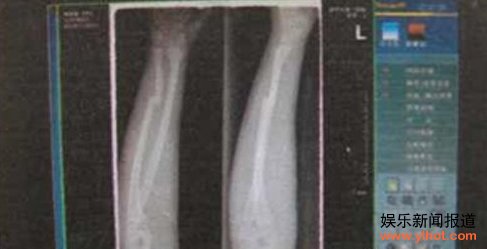

有“碰瓷”人从人贩子手中买来13岁少年,骗其吸毒,趁其昏倒,残忍打断其左手,在南平建阳高速路口附近制造假交通事故,向过路车主诈骗高额医疗费。